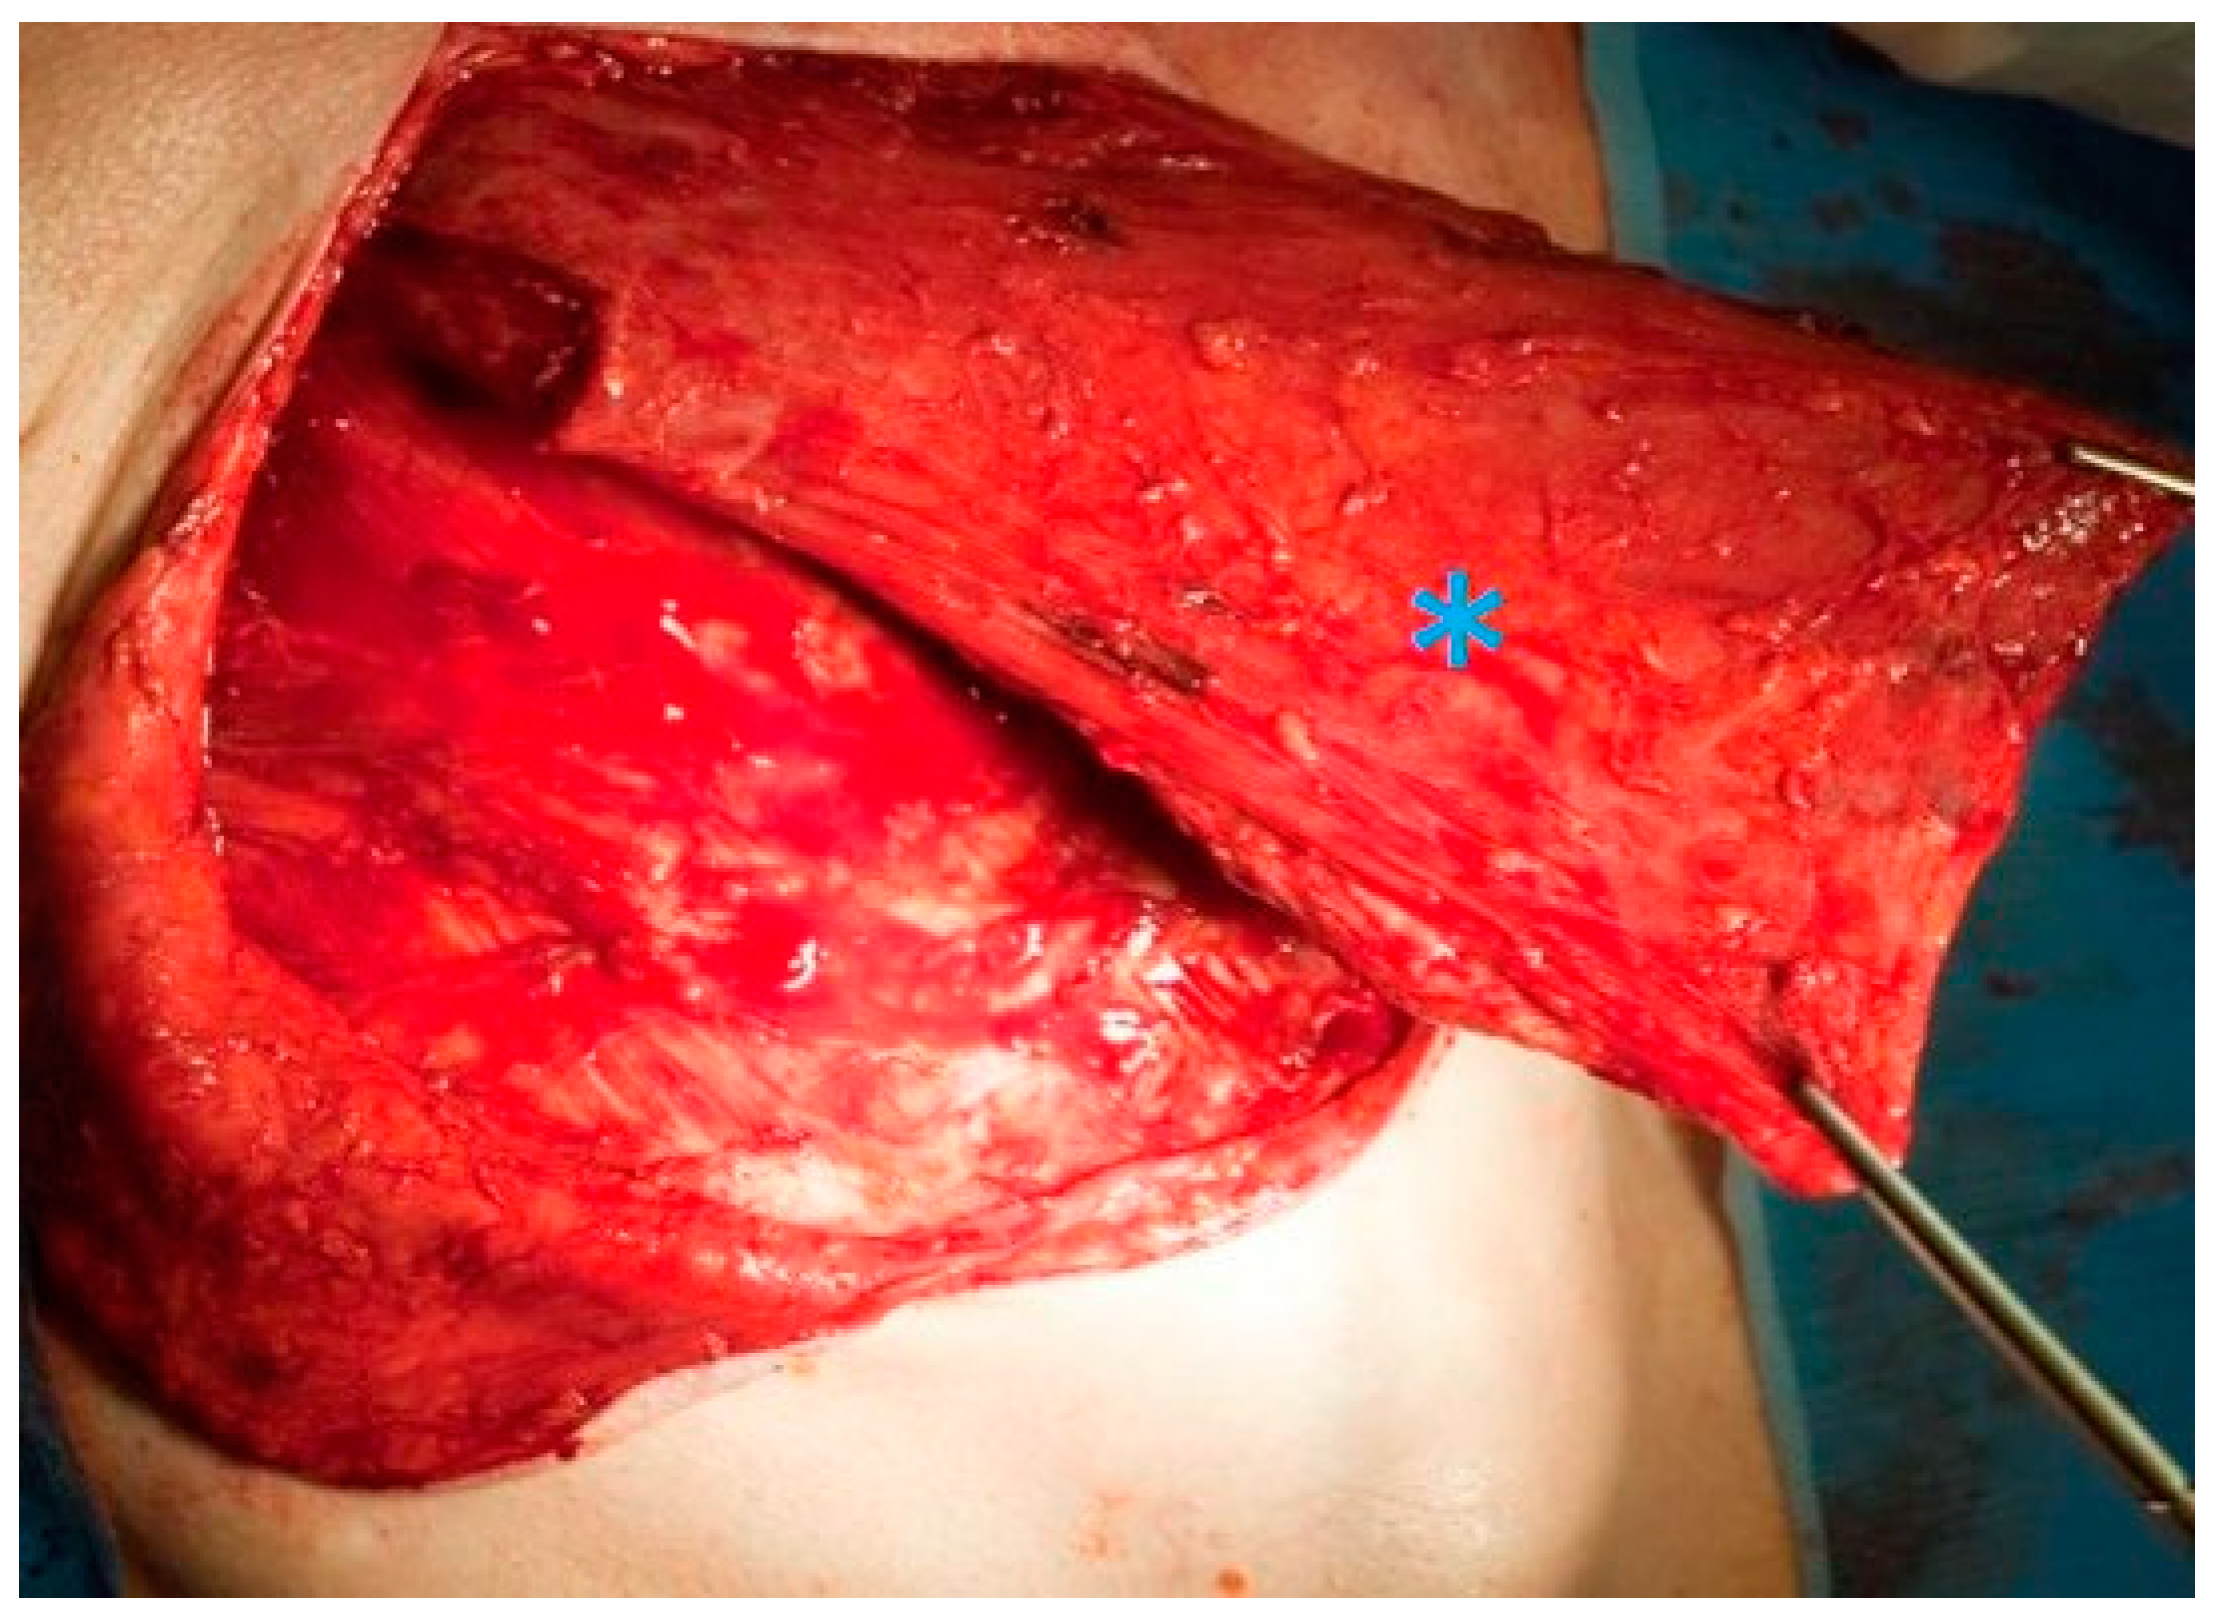

2.2. Surgical Technique for Total Laryngectomy